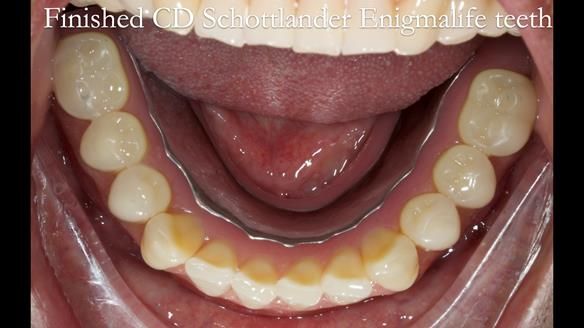

Welcome to Newsletter 62. In this edition, I walk through the process of removing 5 upper anterior teeth, adding to an existing upper RPD, followed by creating and fitting metal based complete dentures for Rafique, a 71 year old man.

The detailed clinical situation and treatment process are outlined below, with clinical work provided by me and technical work by Rowan Garstang. The treatment spanned 12 months, involving removing 5 upper anterior teeth, adding to an existing upper RPD, followed by creating and fitting metal based complete dentures.